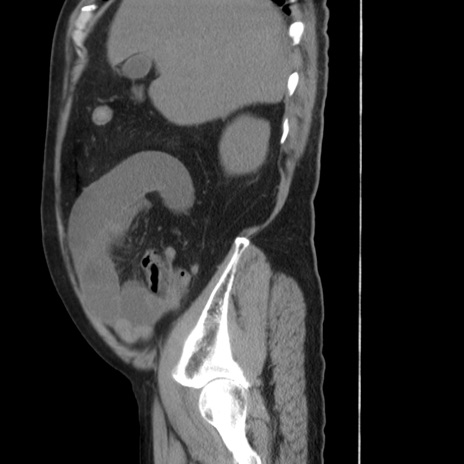

症例20(矢状断像)

【症例】 60歳代男性

【主訴】 腹部膨満、嘔吐

【現病歴】5日前頃より倦怠感を認め食事量減少し4日前の朝嘔吐、食事摂取困難となった。 3日前近医受診し点滴施行され整腸剤などを処方された。 当日他院を受診し、腹部膨満著明、炎症反応の上昇(CRP10.8、WBC11200)あり、紹介受診となる。

【身体所見】 意識JCS1 受け答えがはっきりしないBP 111/57mHg、 P 67bpm、、BT35.2°C、SpO2 97%(RA)、 腹部:膨隆、打診で鼓音あり、全体的に圧痛有り、腸蠕動音(-)、反跳痛ははっきりせず。

【データ】WBC 11400、CRP 14.20